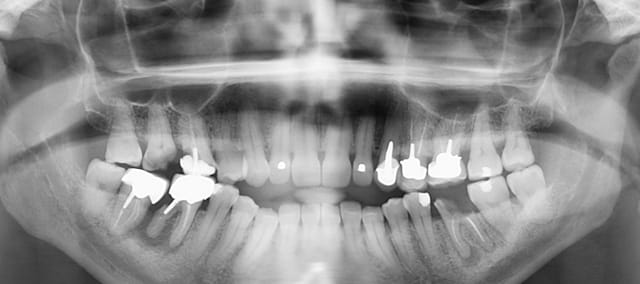

Urgence de 17h ……vient pour receler 36

36 46 47 ont été faites il y a 8 ans

24 25 26 il y a 2 ans (magnifique traitement de la 24).

A vu un prat il y'a 2 ans pour abcès sur 46 / réponse du prat : tout va bien par contre faut vite couronner 24 25 26.

Quand je vous dis que c'est TOUS LES JOURS !!!!!

C'est tout simplement une honte

Je trouve les endos correctes. Supérieures à la moyenne. -))))